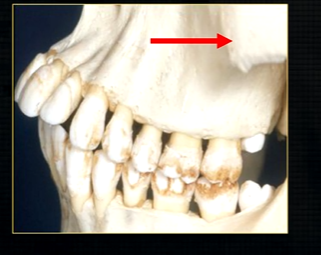

what can you say about the surface anatomy of the maxilla around the teeth themselves?

very undulating - prominences over roots

bony spike of the anterior nasal spine

becomes visible at the side view

posteriorly, the maxilla….

widens as it articulates with the zygoma or cheekbone

The zygomatic buttress is a key vertical support structure of the midface, formed by the junction of the zygomatic process of the maxilla and the zygomatic bone